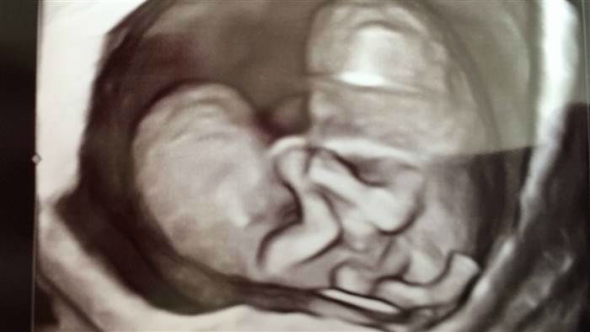

Челси Торрес сейчас на 26-й неделе беременности. Она вынашивает сиамских близнецов, которым уже придумала имена: Колли и Картер.

Девочки соединены в области живота, у них две ноги на двоих — по одной на каждую. Но у каждой есть обе руки.

"У них общая печень и диафрагма. Две почки — тоже по одной на каждую. У девочек общий мочевой пузырь и сплетенные кишечники, два отдельных сердца и желудка. Врачи еще не уверены, один ли у них таз на двоих или два. Мы узнаем это, когда они появятся на свет и можно будет сделать рентгеновский снимок. Врачи сделают трехмерную модель области таза, чтобы понять, как лучше разделить девочек".